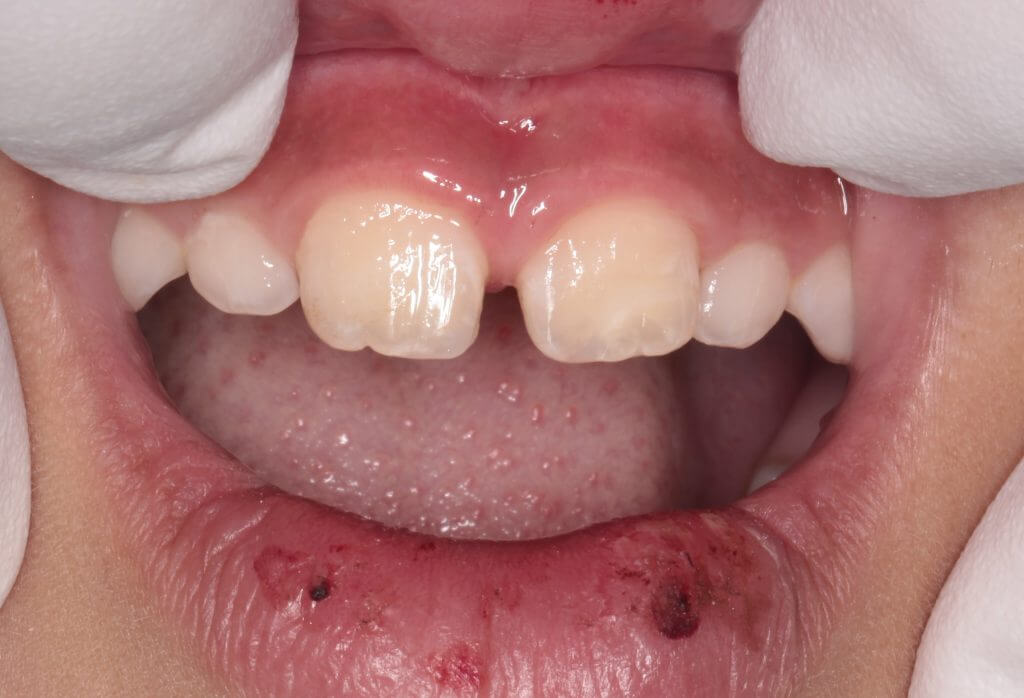

朝、子供が学校への登校中に前歯を強打したということで来院

お母さんが心配されて来院されました。

歯牙の破折は右側と左側に認められます。

口腔内所見では露髄は認められず臨床症状もないため神経には問題はなさそうでした。レントゲン所見でも問題なかったので修復処置に移ります。今回は左側の大きく欠けた歯の一部をお母さんが探して持ってきていたので、それをコンポジットレジンで接着して修復の一部に再利用することとしました。